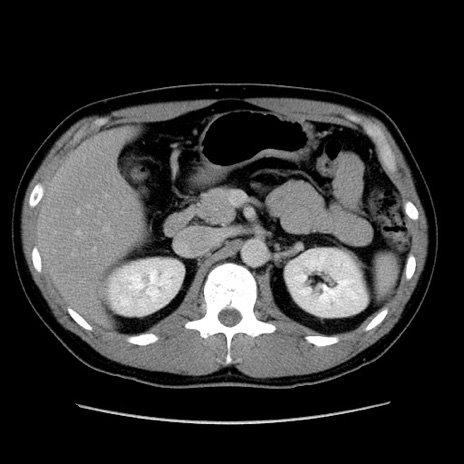

冠状断像

【症例】30歳代男性

【主訴】腹痛、嘔吐

【現病歴】昨晩から突然の腹痛あり、その後嘔吐、軟便も出現。腹痛が改善しないため救急搬送となる。2日前にしめ鯖の食事歴あり。

【身体所見】意識清明、苦悶様、BP 135/90mmHg、BT 35.7℃、腹部:平坦、やや硬、心窩部〜臍部に自発痛、圧痛あり、筋性防御+、反跳痛-

【データ】WBC 8100、CRP 0.57